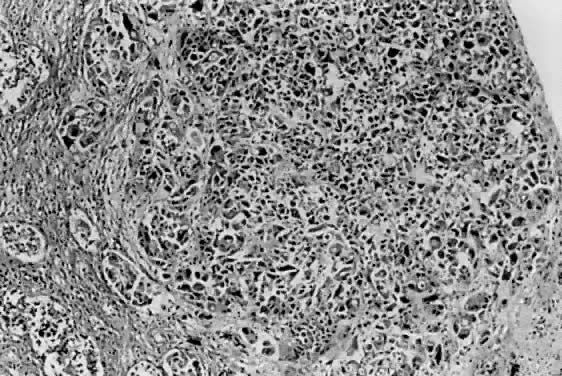

Tumors lacking definitive glandular or squamous differentiation are termed undifferentiated carcinomas. This group is often divided into large and small cell categories.54 Small cell carcinomas range histologically from diffuse sheets of poorly differentiated cells (Fig. 16), similar to small cell carcinomas of other locations, to patterns simulating carcinoid tumors.55 Reactivity with neuroendocrine antibodies is not uncommon in the small cell group.54,56 Also described in the literature are undifferentiated carcinomas with multinucleated giant cells,57 occasionally resembling osteoclast-like giant cells. The prognosis is comparable to a grade 3 endometrial carcinoma, regardless of small or large cell morphology.

Fig. 16. Small cell carcinoma is characterized by sheets of round to oval cells with granular chromatin and often dot-like nucleoli. The mitotic rate is quite high in these clinically aggressive lesions.